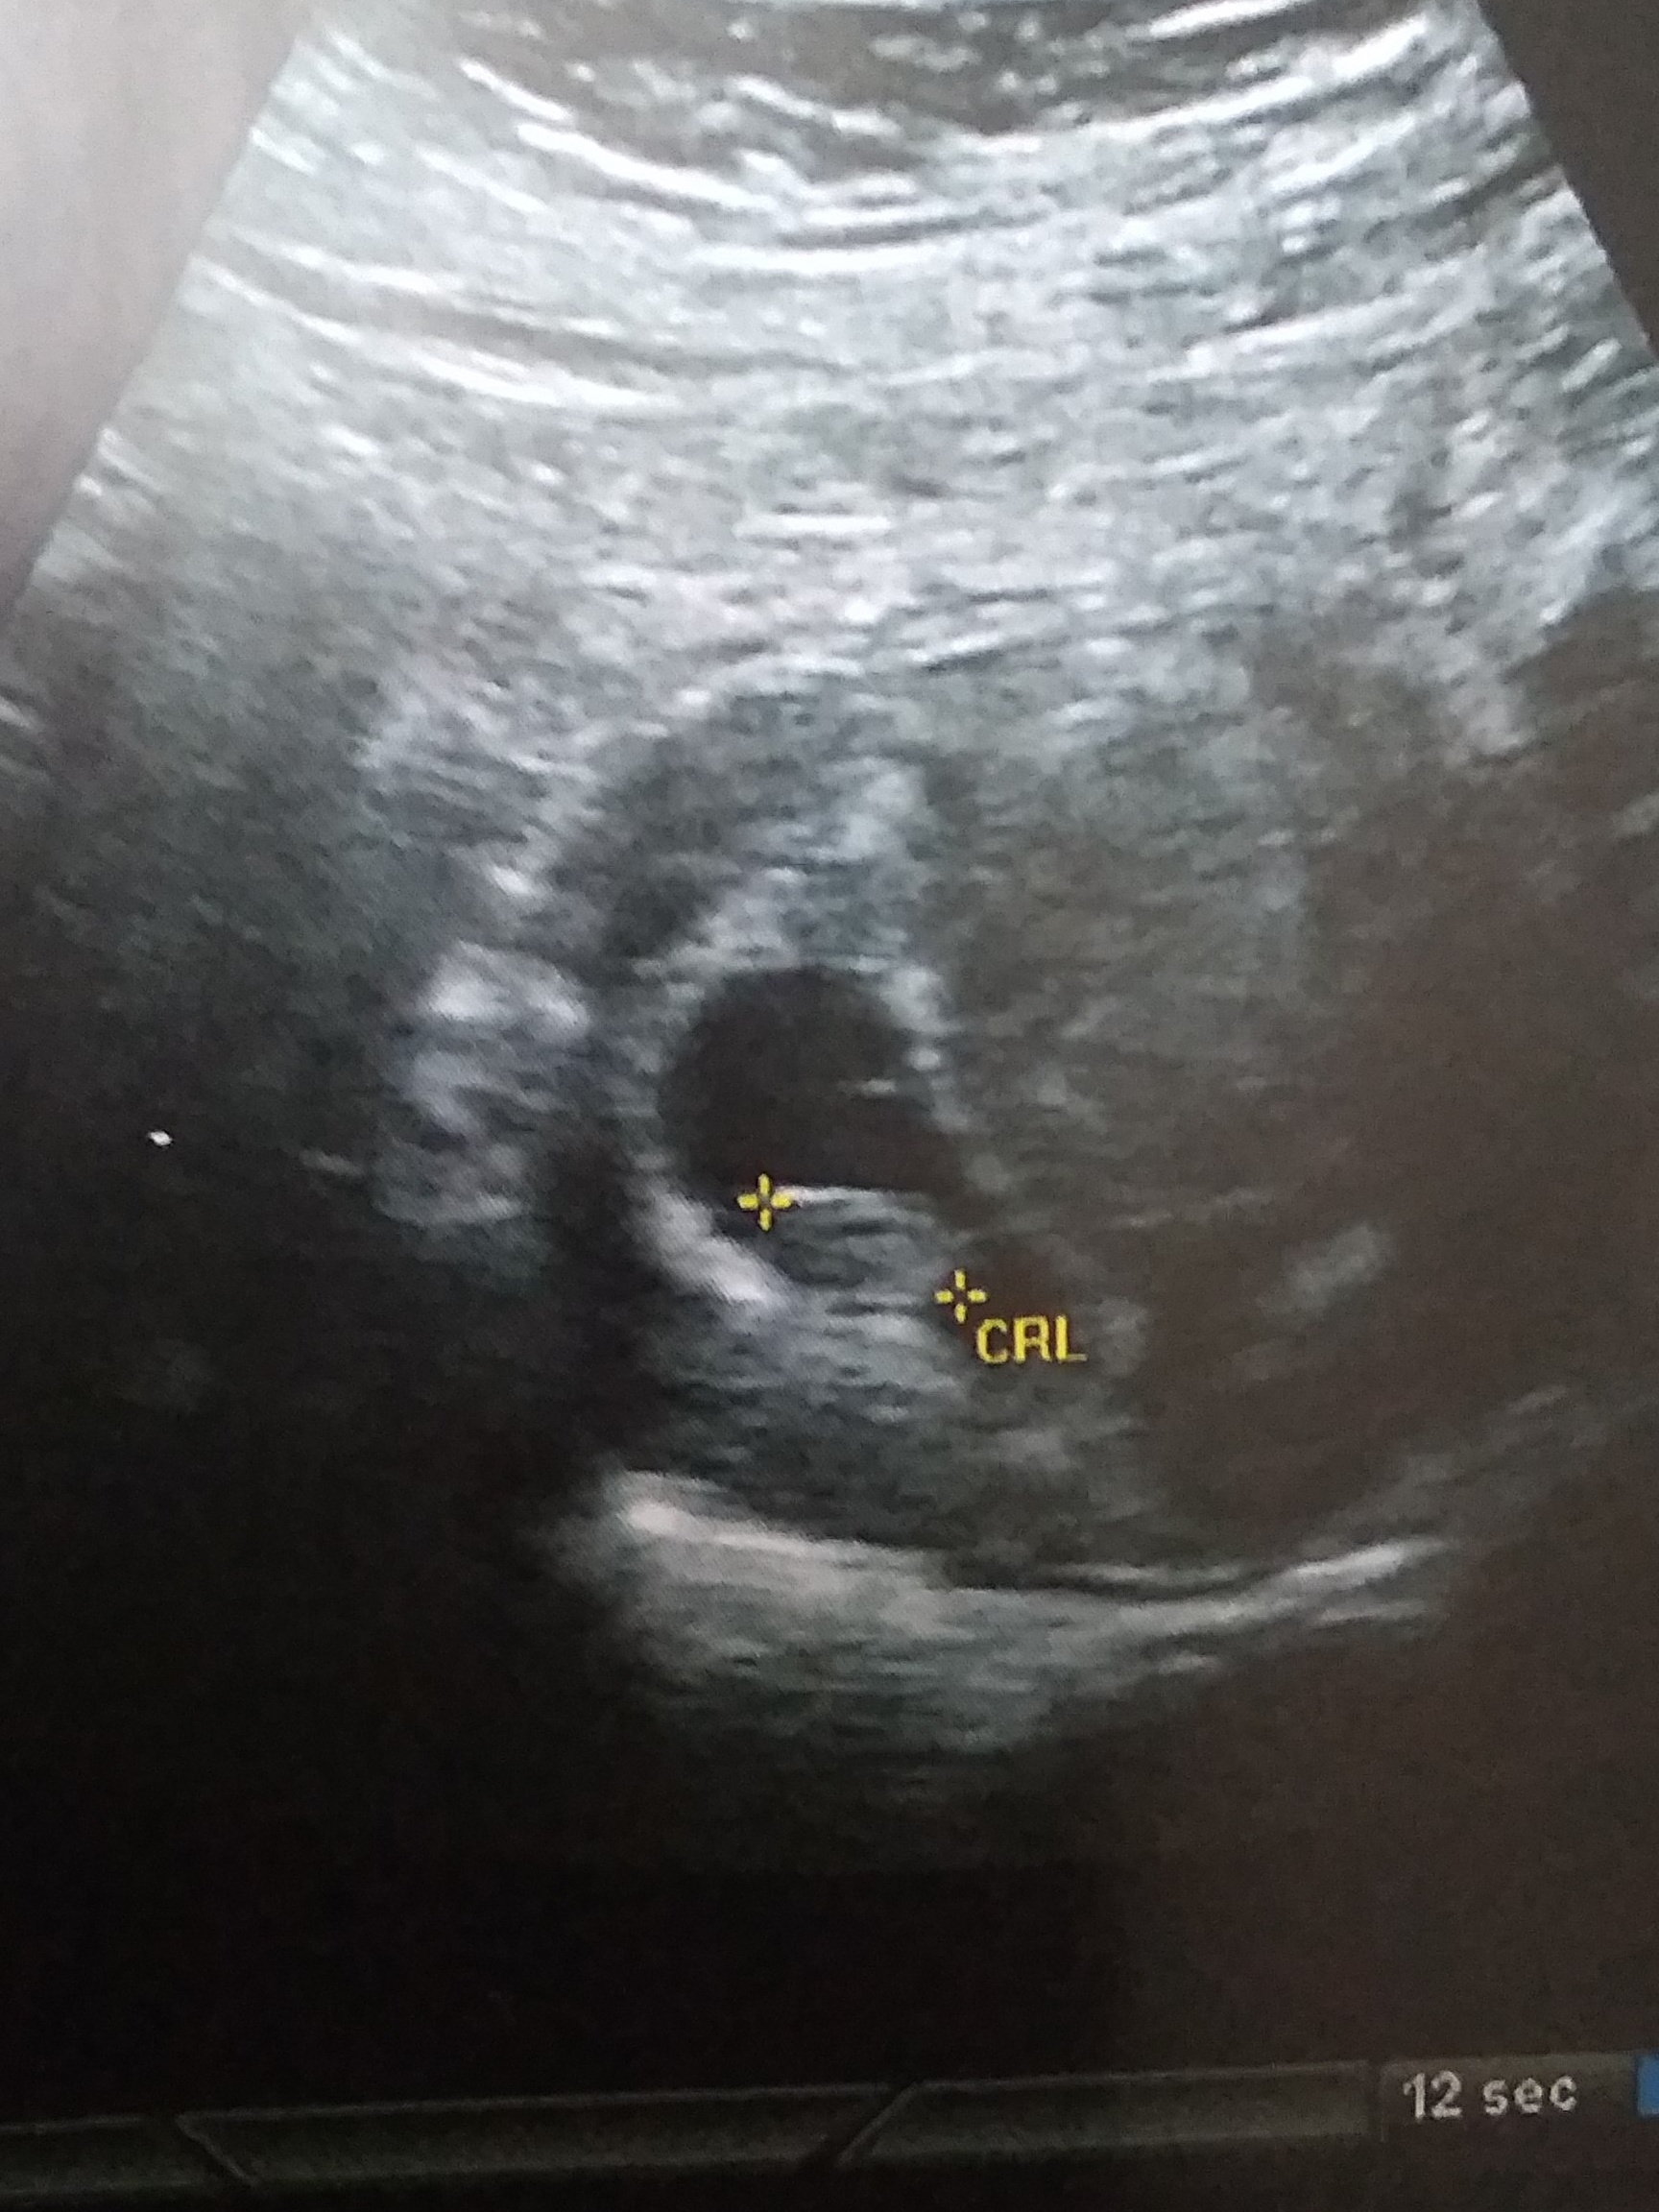

This is a abdominal scan taken at 8weeks. Any guesses, boy or girl??

I thought ramzi will be good from 6-8 weeks. Just for fun!